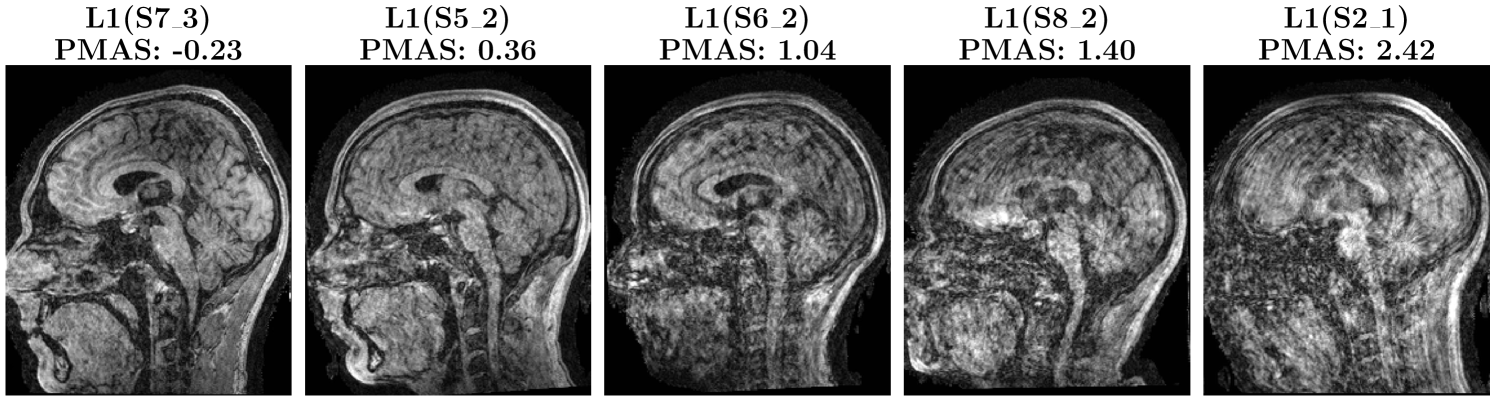

Training samples are triplets Ref,C1,C2Refsubscript𝐶1subscript𝐶2\bigl{\langle}\text{Ref},\,C_{1},\,C_{2}\bigr{\rangle}⟨ Ref , italic_C start_POSTSUBSCRIPT 1 end_POSTSUBSCRIPT , italic_C start_POSTSUBSCRIPT 2 end_POSTSUBSCRIPT ⟩, where Ref denotes the L1-wavelet reconstruction of the original motion-free volume, and C1subscript𝐶1C_{1}italic_C start_POSTSUBSCRIPT 1 end_POSTSUBSCRIPT, C2subscript𝐶2C_{2}italic_C start_POSTSUBSCRIPT 2 end_POSTSUBSCRIPT are reconstructions of the same slice under two distinct motion severities. For example, if the severity of C1subscript𝐶1C_{1}italic_C start_POSTSUBSCRIPT 1 end_POSTSUBSCRIPT lower than that of C2subscript𝐶2C_{2}italic_C start_POSTSUBSCRIPT 2 end_POSTSUBSCRIPT, then Ref should be closer to C1subscript𝐶1C_{1}italic_C start_POSTSUBSCRIPT 1 end_POSTSUBSCRIPT. An example of the triplet is shown in Figure 6.

Refer to caption

Figure 6: Example triplet from the MoMRISim training dataset. The left image is corrupted by motion (severity level 3) and reconstructed using a 2D U-Net. The right image is corrupted by more severe motion (level 6) and reconstructed with an L1 reconstruction without motion correction. The center image is a motion-free reconstruction using an L1 reconstruction.